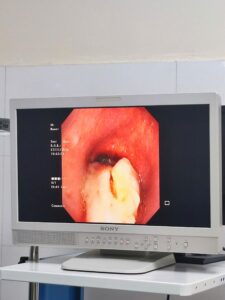

Tổ chức gây bít tắc 90% lòng khí quản

Người bệnh nhanh chóng được chuyển đến khoa Hồi sức tích cực Bệnh viện Phổi Trung ương trong tình trạng lơ mơ, suy hô hấp nặng. Tại đây các bác sỹ đã khẩn trương nội soi ống cứng cấp cứu và sử dụng điện đông cao tần để làm sạch tổ chức bít tắc. Đây cũng là một trong những kỹ thuật thế mạnh của Bệnh viện Phổi Trung ương, kỹ thuật này đã giúp cứu sống cho hàng nghìn người bệnh có hẹp và khối u trong đường thở lớn.